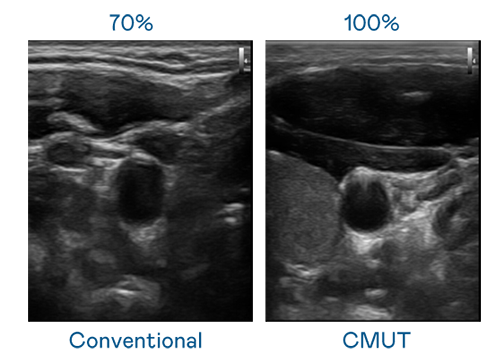

CMUT 技术是一种用电容式微机电元件来产生超音波讯号的技术。与传统 PZT 压电式技术相比,CMUT 频宽增加 30%,更宽频的超音波讯号让影像解析度大幅提升,是实现高影像品质医疗超音波扫描、促进精准医疗发展的关键技术。

超音波影像的解析度高低,首先取决于探头能发出的讯号频宽。维多利亚老品牌vic119 CMUT 可提供高清晰的超音波讯号,提供高频宽、高灵敏度、影像纹理细节更高的超音波影像,协助医护人员缩短影像判读时间及利用精准的医疗影像进行诊断。